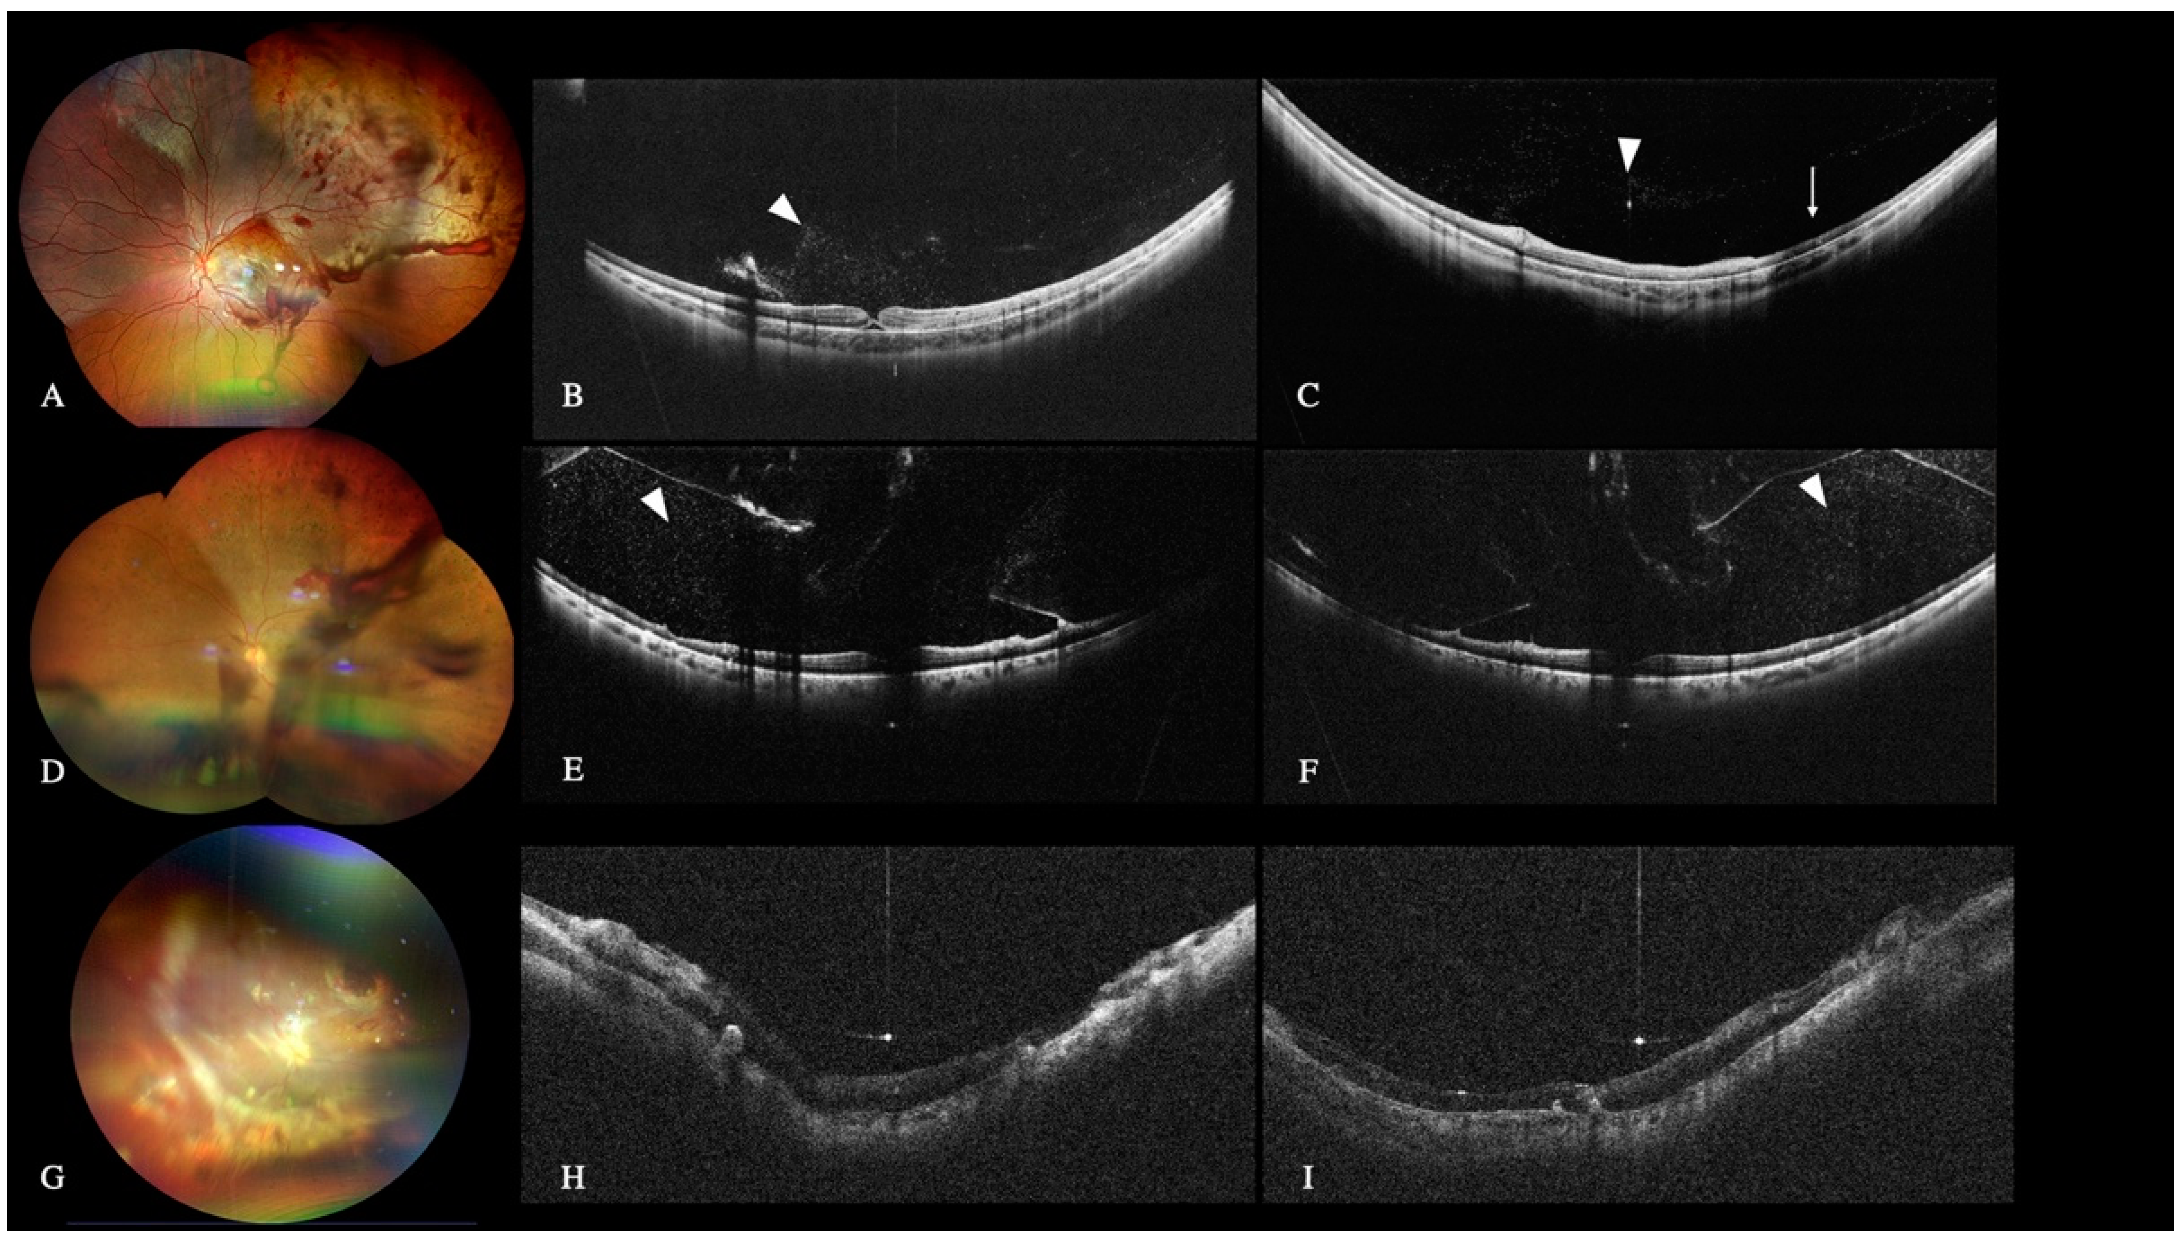

3.3.2. Retinal Detachment

3.7.2. Media Opacities

3.7.3. Pediatric Cases

3.7.4. Postoperative Follow-Up